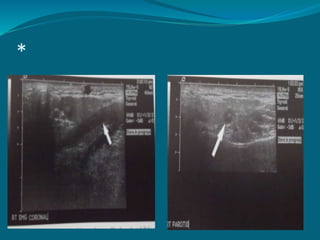

*

Benign tumour Sialolith